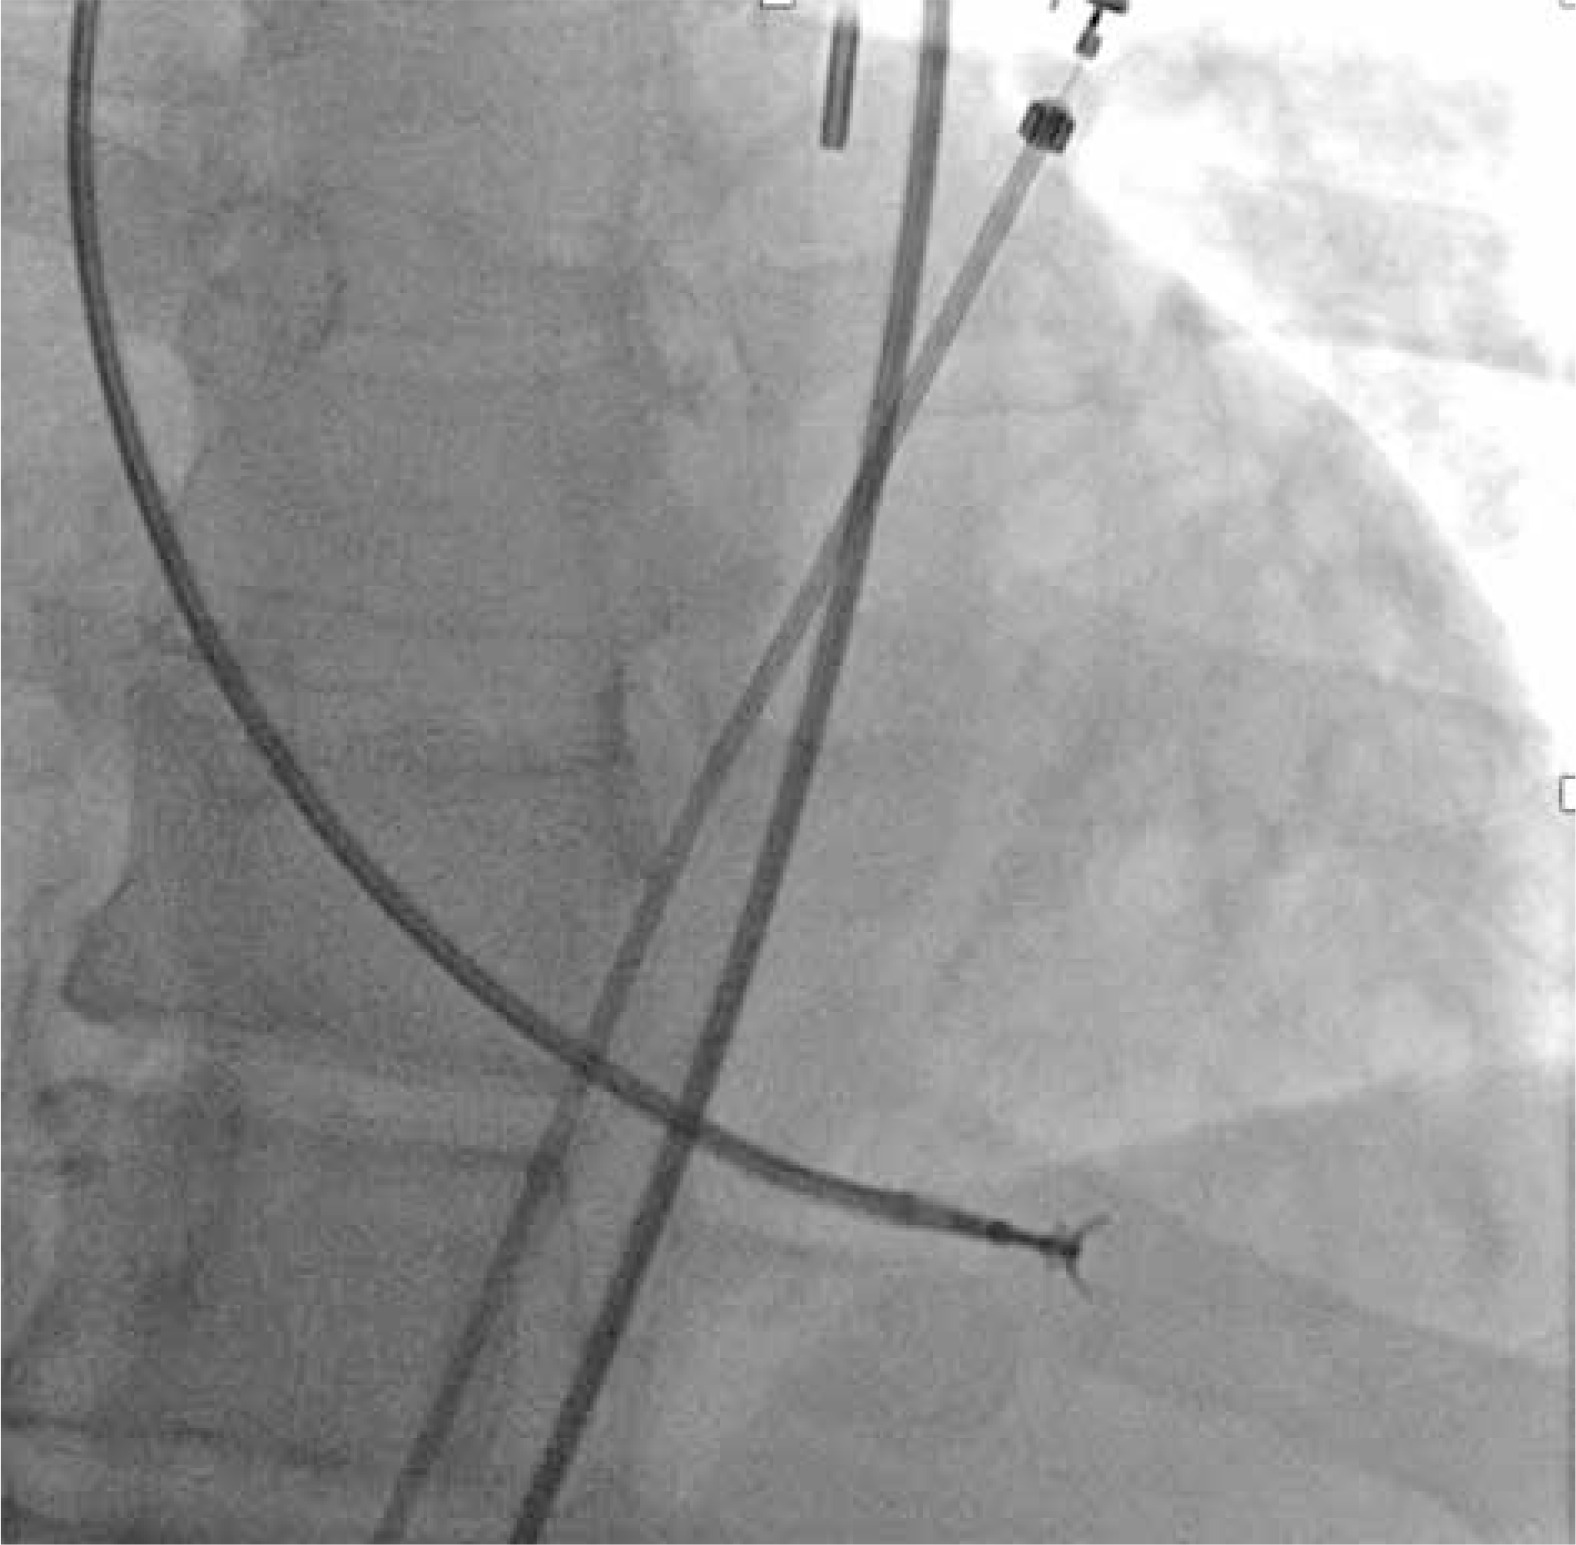

The arterial puncture was performed under local anesthesia in the supine position. The prepared biopsy equipment is shown in Figure 1. After the femoral artery puncture, an arterial sheath, initially 8-French (Fr) and now 7-Fr (Balton, Poland), was introduced. After placement of the arterial sheath, each patient received a bolus of unfractionated heparin (3000–5000 IU) to achieve an activated clotting time (ACT) of 200–250 s. In our study, a total of 16 combined coronary angiographies followed by EMB were performed.

After femoral artery puncture, a 5-Fr pigtail catheter (Boston Scientific, USA) was introduced through a guidewire into the left ventricular lumen via the aortic valve. Then a long J-guide (260 cm, 0.03500) was advanced through the catheter into the LV lumen. The pigtail catheter was removed from the ventricle, and a 90 cm long, 7-Fr MB or JR guiding catheter (Medtronic, USA) was introduced. Subsequently, the J-guide was removed, and a Y-connector was connected to the catheter.

The optimal position and distance between the tip of the guiding catheter and the lateral wall of the LV were checked in the left oblique 20° projection by injecting 5–6 ml of contrast medium. The tip of the catheter should optimally point to the left at the free (lateral) wall of the LV, but it should not touch it (Figure 2). After checking the location of the catheter, 104 cm long Cordis (USA) 5.5 F biopsy forceps were inserted under fluoroscopy guidance near the tip of the guiding catheter. Afterwards, they were opened while still inside the guide catheter and carefully moved toward the lateral wall of the LV (Figure 3). After taking the sample, the closed biopsy forceps were withdrawn slowly into the guide catheter under fluoroscopy control. In total, 6–9 biopsy specimens of 1–2 mm in size with a material volume of approximately 2.4 mm2 were taken from different sites of the LV. To avoid air embolism, before each insertion of the bioptome into the catheter, the forceps were thoroughly rinsed with saline solution.